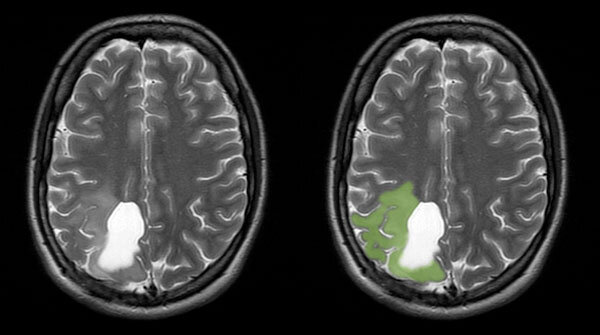

Living with a slow growing brain cancer

Note: I started blogging about brain cancer in 2008, at age 29.